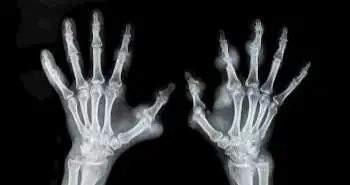

This study summarizes the evaluation of abatacept efficacy among 35 RA patients through magnetic resonance imaging (MRI) of bilateral hands. The MRI evaluation was done at baseline and after 12months of abatacept treatment. The MRI images which were taken into account for evaluation were erosion, synovitis, joint space narrowing (JSN) and osteitis. The RA MRI Scoring System (RAMRIS) was used to rank these images. The change in RAMRIS score was considered as the primary endpoint.  The repair of erosion also noticed after the treatment. This was the negative change in the erosion scores which were noticed higher than the smallest detectable changes (SDCs).

Out of 35 patients, 31 finished the treatment therapy. The osteitis and synovitis scores exhibited a great statistical decrease at 12th month. On the other hand, no changes were seen in  JSN and median erosion scores. Only 11% of participants exhibited repair of erosion & obtained a functional remission. However, 83% of participants reflected no change in erosion scores. The study evaluated the Simplified Disease Activity Index response rate in the first month of treatment as an independent factor which predicted changes in the erosion scores after 12-month treatment.